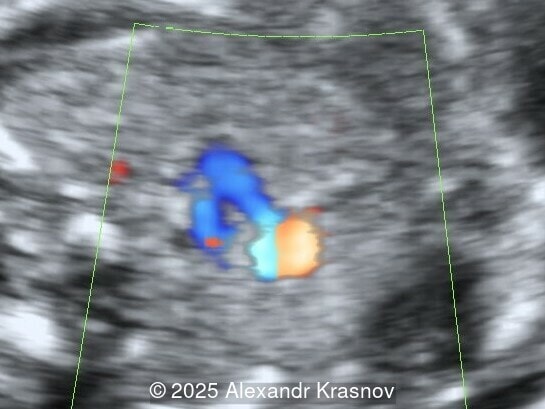

Our ultrasound showed biometry data corresponding to 21 weeks of gestation. During echocardiography, an abnormal drainage of the pulmonary veins was detected in which the pulmonary veins drain into a venous collector linked to the superior vena cava. The four-chamber view and the three-vessel view were altered and raised suspicion of a pathology. The grayscale and color Doppler images of the four-chamber view indicate a smooth posterior wall of the left atrium, increased distance between the left atrium and the descending aorta and the absence of pulmonary veins entering the left atrium (Image 1, 2; Video 1, 2). In the three-vessel view, the diameter of the superior vena cava appears larger than that of the aorta (Image 3, Video 3). In the images of the venae cava, a significant difference is seen between the diameters of the inferior and superior vena cava with significant enlargement of the superior vena cava (Image 4, Video 4). Additionally, there is a pulmonary venous confluent chamber (“twig sign”) behind the left atrium (Image and Video 5). A vertical ascending vein connects the confluent chamber with the superior vena cava where it drains blood from the pulmonary veins (Images 6, 7; Video 6).

Direct markers are based on anatomical features in TAPVR, and their presence usually confirms the diagnosis. Some appear in all types of TAPVR, and others are specific to particular types. A lack of connection between the pulmonary veins and the left atrium or the presence of a confluent chamber can be found in all types of TAPVR. Whereas the presence of an ascending or descending vertical vein is found in supracardiac or infracardiac types. Normal entry of a left and right pulmonary vein at the posterior wall of the left atrium (horn‑like insertion) is absent, which leads to a completely smooth posterior wall in the four-chamber view [6,7]. The “twig sign” represents the entry of the pulmonary veins into a confluent chamber behind the left atrium [7], and is visible in the four‑chamber view except in the cardiac type. In the cardiac type, the confluent vein is located more inferiorly, below the plane of the four‑chamber view and does not form a twig sign, making it more difficult to detect [5]. In supracardiac TAPVR, an ascending vertical vein can be observed in the 3-vessel tracheal view as an additional vessel, usually located at the left of the main pulmonary artery. In infracardiac TAPVR, the descending vertical vein can be seen as an additional vein in the axial abdominal plane [8].

In many cases, direct signs are not visualized, thus identification of indirect signs allow us to suspect this pathology, not diagnose it. They are based on morphological findings such as increased post‑left atrium space, or on hemodynamic changes such as ventricular disproportion, dilated superior vena cava or coronary sinus, and abnormal Doppler waveforms. The presence of a pulmonary venous confluence leads to an increased distance between the left atrium (LA) and the descending aorta (DAo) [9]. While visualization of the confluent chamber may be difficult, objectively measuring the increase in the space behind the left atrium in an axial section may be easier to verify. Various indices have been proposed for this purpose, the most widely used being the “post‑LA space index” described by Kawazu et al [10]. It is calculated as the ratio of the LA‑DAo distance to the diameter of the DAo, proposing a value ≥1.27 as a potential marker of TAPVR. In clinical practice, a cut-off of 1.0 may be more useful to increase detection rates, although this would be at the expense of more false positives. An alternative marker with a similar diagnostic performance and independent of the gestational age is the “left atrial posterior space to diagonal ratio,” which is calculated by dividing the LA‑DAo distance by the left atrial diameter, with an optimal cut-off ≥0.35 [11]. Asymmetric ventricular chamber dimensions with right heart dominance result from extra‑abnormal flow from the pulmonary veins to the right heart, providing a diagnostic clue for TAPVR [9], but this finding is late and not very specific. In supracardiac TAPVR, anomalous pulmonary venous drainage increases blood flow to the collector, which travels to the right atrium through the dilated innominate vein and superior vena cava, visible in the three-vessel trachea and bicaval views [7,12]. In the subcostal view of pediatric echocardiography, the cardiac type is characterized by the “whale’s tail sign,” where left and right pulmonary veins drain into the dilated coronary sinus. Although it is a technically difficult plane to obtain in fetal echocardiography, it has been described by Karmegaraj in a 25-week-old fetus [13]. Spectral Doppler waveforms are typically normal or biphasic in cardiac type, whereas in supracardiac and infracardiac types, the waveforms can be biphasic, monophasic, or continuous [6,7]. Color and spectral Doppler assessment allows the identification of the fetuses with pulmonary venous pathway obstruction and, therefore, at risk for acute postnatal deterioration with severe respiratory distress and cyanosis [14].